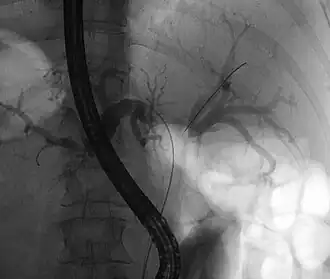

Tumeur de Klatskin lors d'une rectocolite hémorragique (absence de contraste

dans la zone de confluence).

La tumeur de Klatskin, ou cancer du hile du foie, est un cholangiocarcinome qui se développe au niveau de la convergence des canaux hépatiques gauche et droit[1]. Il y a progressivement obstruction des canaux hépatiques gauche, droit et commun avec développement d'un ictère. L'envahissement de voisinage se fait dans les segments hépatiques proches du hile comme le IV, le III et le V.

- Cholangiographie rétrograde : identification de l'obstacle